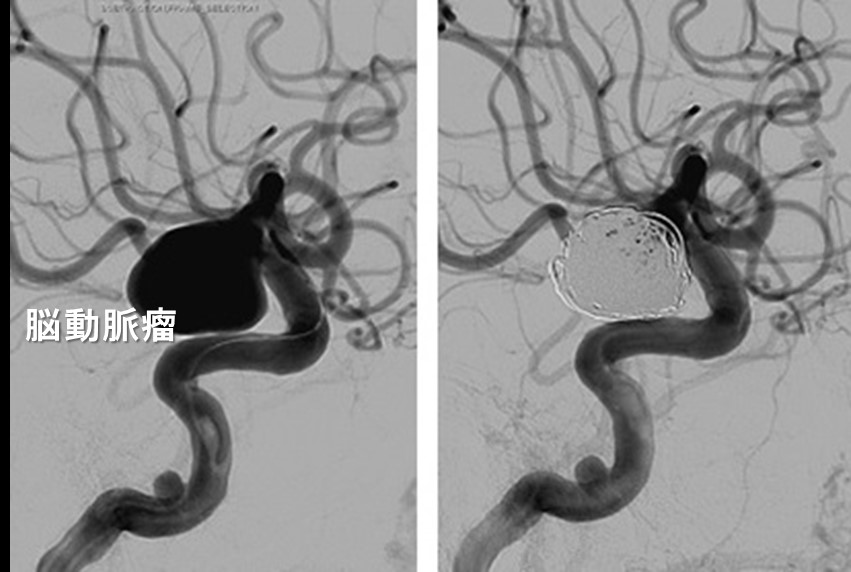

再出血予防の治療には2つの方法があります。一つは、開頭手術(クリッピング術)、もう一つは、カテーテル手術(コイル塞栓術)です。クリッピング術とは動脈瘤の根っこのところを小さな金属製クリップで挟んで、動脈瘤に血流が入らないようにします。動脈瘤の大きさや位置、周囲の血管との関係から動脈瘤の根っこをクリップで挟むことができないこともあり、その場合は動脈瘤壁を補強する処置を行います。一方、コイル塞栓術は、カテーテルを用いて瘤の内部に金属でできたコイルと呼ばれる細くて柔らかいワイヤーを充填し、動脈瘤の中に血流が入らないようにします。クリッピング術とコイル塞栓術にはそれぞれに利点、欠点があり、どちらが適しているかは多くの要素を考慮して判断する必要があります。数日以内の再破裂が多いので、通常の場合は発症から2日以内に手術をします。

図:動脈瘤コイル塞栓術 左(コイル塞栓術前)右(コイル塞栓術後)